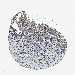

CERVICAL CANCER - Protein expressioni

A mouse-over function shows sample information and annotation data. Click on an image to view it in a full screen mode. Samples can be filtered based on level of antibody staining by selecting one or several of the following categories: high, medium, low and not detected. The assay and annotation is described here.

Note that samples used for immunohistochemistry by the Human Protein Atlas do not correspond to samples in the TCGA dataset.

Antibody stainingi

Antibody staining in the annotated cell types in the current human tissue is reported as not detected, low, medium, or high, based on conventional immunohistochemistry profiling in selected tissues. This score is based on the combination of the staining intensity and fraction of stained cells.

Each image is clickable and will lead to virtual microscopy that enables deeper exploration of all samples and also displays staining intensity scores, fraction scores and subcellular localization as well as patient and tissue information for each sample.

Antibody HPA018990

Antibody HPA018993

Antibody HPA018996

Antibody HPA024089

Staining

High

Medium

Low

Not detected

Intensity

Strong

Moderate

Weak

Negative

Quantity

>75%

75%-25%

<25%

None

Location

Nuclear

Cytoplasmic/membranous

Cytoplasmic/membranous,nuclear

Squamous cell carcinoma, NOS

Adenocarcinoma, NOS